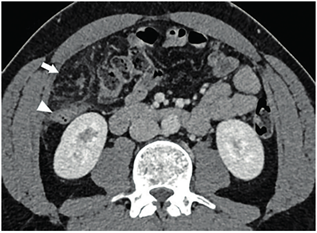

Ante la persistencia del dolor se decidió complementar los estudios con tomografía computarizada de abdomen con y sin contraste intravenoso (Figuras 1 y 2) donde se aprecia infarto del omento, para lo que se inicia tratamiento médico conservador. Luego de 24 horas aumenta el dolor abdominal, por lo que se realiza laparoscopia exploradora. En el intraoperatorio, se confirma necrosis del sector superior derecho del epiplón mayor; se realiza la resección con ligasure® (Figura 3). Tuvo buena evolución posoperatoria, dando de alta a las 48 horas. La anatomía patológica confirmó el diagnóstico de infarto omental.